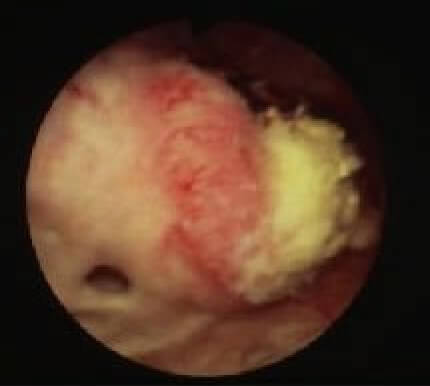

膀胱鏡で見ると、表在性膀胱がんは柔らかくイソギンチャクのような形態(乳頭状)をしています。一方、浸潤性膀胱がんは硬く岩山のような形態(広基性)をとります。しかし、正確な病期を決定するためには、膀胱鏡により組織を採取(生検)して顕微鏡で調べることが必要です。

表在性膀胱がん

浸潤性膀胱がん